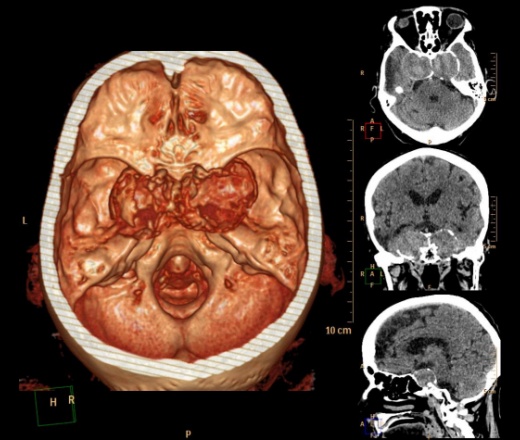

А контраст почему не делали? Больше похоже на тромбированные аневризмы

Неужели такие аневризмы? Бывает же! А сканы с контрастом есть?

Макроаденома гипофиза с интра-эндо-супра-и латероселлярным ростом,инвазией кавернозных синусов и зрительной хиазмы.

В первую очередь подумала бы о менингиоме бугорка турецкого седла или передних наклоненных отростков. Дифференцировала бы с краниофарингиомой но смущает форма.

Да простят моё нахальство уважаемые специалисты КТ. Я вижу тут огромные инкапсулированные узлы расположенные почти симметрично справа и слева от турецкого седла, которое разрушено узлом поменьше. Латеральные злы продавливают дно средней черепной ямы. По-видимому, здесь доброкачественная опухоль типа «аденома», исходящая из гипофиза и давно растущая. Обызвествление есть не только в капсулах узлов, но и в их толще (очаговое). При таких размерах узлов и косных разрушениях, нет сомнения, пострадали и зрительные нервы.

Неоднозначно всё

Цифровых и плёночных доказательств на руках нет. Опухоль диагностирована в 2004 году, размером "с вишню", дебютировала птозом века правого глаза, умеренной головной болью в лобной области слева и постепенным снижением зрения, катаракта. Пациентка с трезвом уме и превосходной памяти (на мой субъективный взгляд))). В выписке результаты КТ, МРТ: неоперабельная опухоль селлярно-параселлярной области с прорастанием кавернозных синусов, аневризма сифона внутренних сонных артерий. Цитологию НЕ брали.

Не совсем понятно, опухоль + аневризма или как?

Да, опухоль, в толще которой аневризма сифона ВСА. Причем с обеих сторон.

Аневризмы с обеих сторон или опухоль?

И то, и другое. Доказать без контрастирования не могу. Когда сама впервые увидела, анамнеза не знала, подумала о двусторонней аневризме. И не угадала.

Насчет опухоли у меня большие сомнения. То что седло растянуто, еще не показатель. Седло увеличивается в размерах даже при гипертонии,а тут такие аневризмы. Самой опухоли не видно, в просвете турецкого седла медиальные полюса аневризм. Ну впрочем не так это важно, интерес чисто теоретический, да и верификации видимо не будет. Спасибо большое за демонстрацию.

Случай-таки не верифицированный. Сочетание опухоли с аневрзмами - это очень странно. Боюсь, тут какая-то путаница.

На мой взгляд, случай требует более внимательного рассмотрения и относительно "готового диагноза", и относительно "неоперабельности".